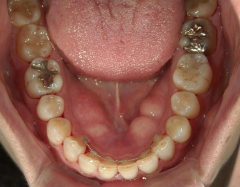

矯正歯科 治療前